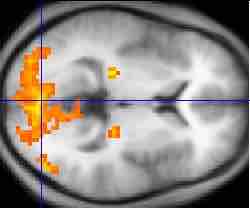

An fMRI of the brain

An fMRI scan showing regions of activation (in orange) including the primary visual cortex.